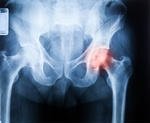

This was a pilot study focusing on people over 70 years old attending the emergency department with Neck of Femur (NoF) fractures. The aim of the trial was to compare two groups of patients while undergoing surgery. One group will have tighter control over their blood pressure while the second group will receive normal care. The study was hoping to prove that tighter intraoperative blood pressure monitoring improves outcomes. We do not have the results of this study yet